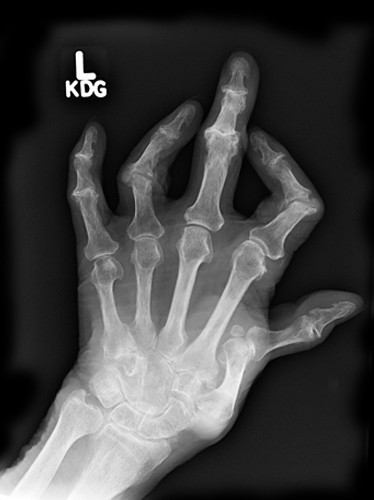

This is a key radiographic appearance to rheumatoid arthritis.

What is rarefaction (dense cortex of bone compared to less dense of medullary cavity)